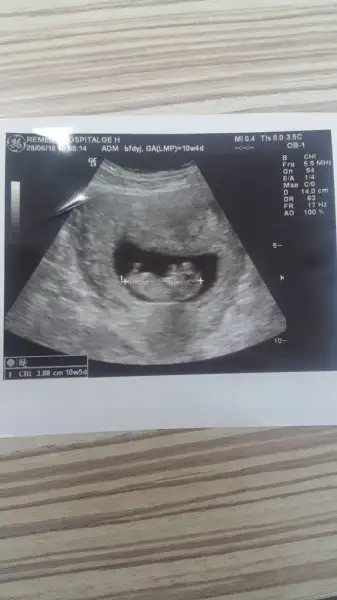

Kızlar ikili test sonuçlarım çıktı. Telefonla aradım doktorumu gayet güzel dedi Cumartesi de kontrolüm var ve sanırım artık cinsiyetini de öğreneceğiz Darısı tüm test sonucu bekleyenlere.. Hepimiz sağlıcakla kucaklayalım yavrularımızı